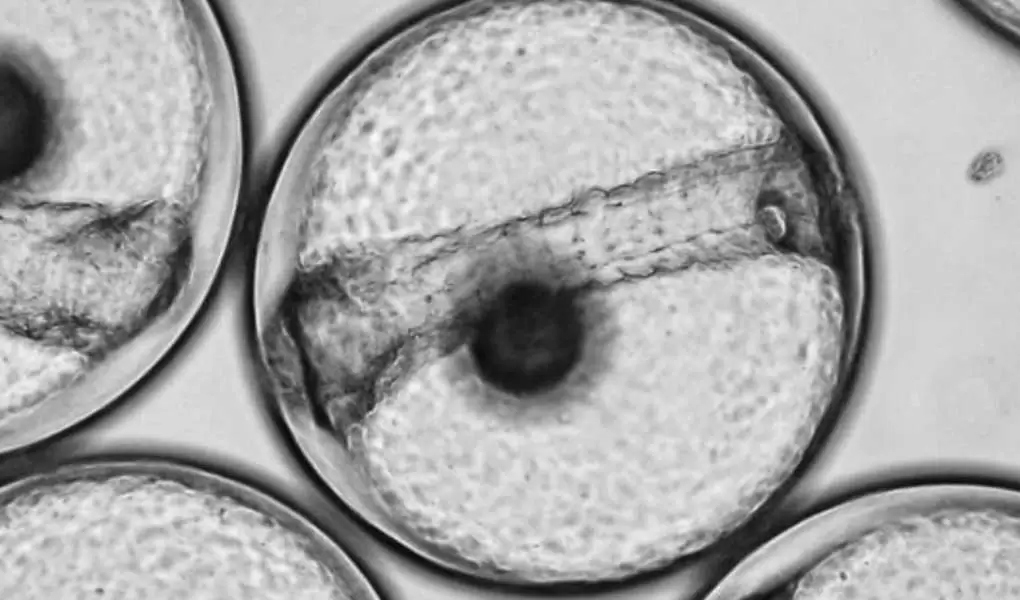

Tüp bebek tedavisinde en yeni tekniklerden biri embriyoların dinamik takibidir. Embriyoscope adlı tekniği Türkiye’ye ilk defa getiren ve uygulayan merkez Bahçeci Tüp Bebek Merkezi’dir. Artık embriyolar takipleri süresince çok kısıtlı bir zaman dilimindeki görüntüleriyle değil her 15-20 dakikada bir videolarla detaylı inceleniyor, kaliteleri buna göre saptanıyor. Bu demektir ki artık embriyoların gelişimleri hakkında çok daha fazla elimizde bilgi birikiyor. Bizim kullandığımız sistem şu anda dünyada bulunan en sofistike dinamik takip sistemidir ve bu sistem sayesinde gebelik başarı oranlarında artış gözlemlenmektedir.